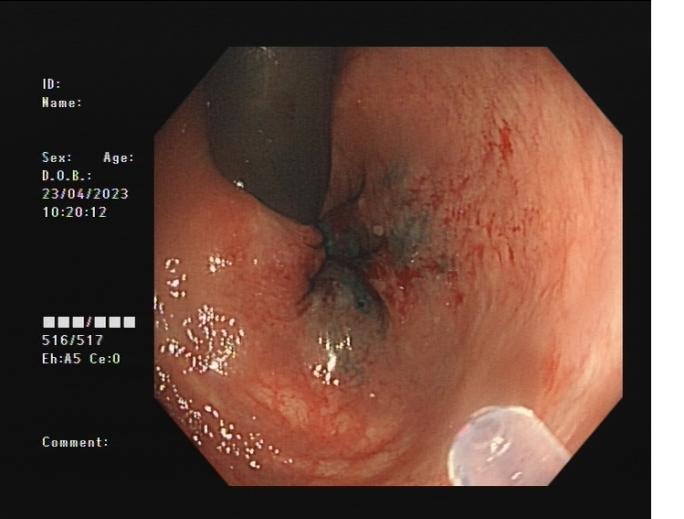

4d818f53b089499c860884ad0d9dab6c.Jpega62e29074df94ee9a5dace0b932c125d.Jpeg

發現內源性低回聲病灶        實時超聲引導下對病灶的細針穿刺活檢

內鏡超聲引導下細針穿刺抽吸術(EUS-FNA):治療對于性質不明的胰腺實性占位性病變;對于經CTMRI或 EUS 等檢查不能確定性質的胰腺囊性病變;對于消化道毗鄰組織中性質不明的占位性病變或淋巴結腫大(如縱隔、上腹部等部位病變);長徑>2cm需要手術切除但具有高手術切除風險,或不能切除的消化道上皮下腫瘤的鑒別診斷。